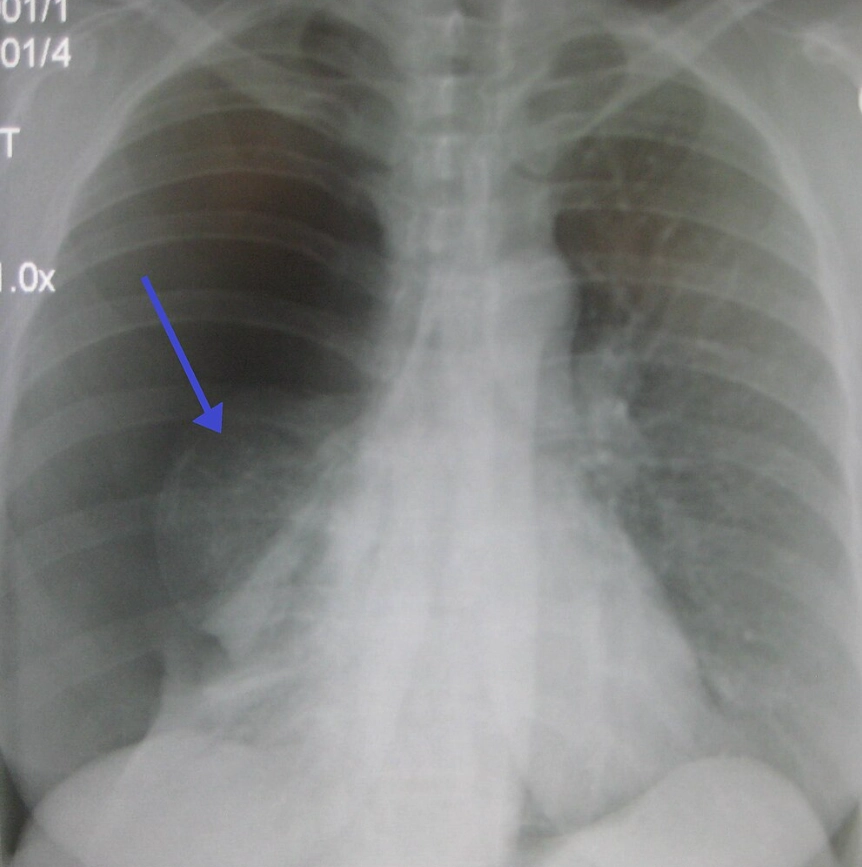

서울아산병원에 따르면 기흉은 폐에 생긴 구멍으로 공기가 새면서 늑막강 안에 공기가 차는 질환을 의미한다. 새는 공기의 양이 증가할수록 폐가 정상 기능을 하지 못한다.

흉강 안으로 유입되는 공기가 배출되지 않는 경우 양쪽 폐와 심장 사이의 공간과 심장이 한쪽으로 쏠려 응급상황이 발생할 수 있다.

기흉의 흔한 증상으로는 흉통과 호흡곤란이 있다. 흉통은 대체로 갑자기 시작되며 24시간 정도가 지나면 사라진다. 일반적으로 “등 쪽으로 담이 결린다”, “숨 쉴 때마다 가슴이 찌르는 듯이 아프다” 등을 호소하는 것으로 알려졌다.

처음 발생한 기흉을 관찰이나 흉관 삽입술만으로 치료한 경우 재발할 확률은 50% 정도이며, 2회에 걸쳐 재발한 경우 3회 이상 재발할 위험이 80~90% 정도다. 따라서 재발한 기흉 환자는 수술 치료를 해야 하며 수술 치료를 받은 환자의 재발률은 5% 정도다.